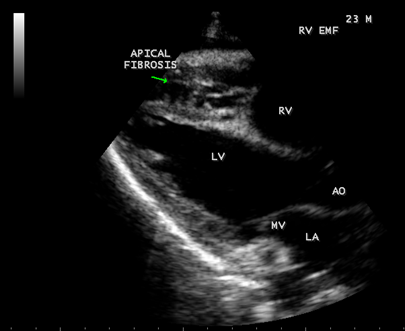

Case 2 (Right ventricular endomyocardial fibrosis in Tuberculosis) A 23-year old male was admitted with sudden onset of ascites for one-month duration. He was treated for pulmonary tuberculosis 3 years back with a positive sputum AFB (acid fast bacilli). Blood chemistry revealed as ( Total count-7400 cells/cu.mm of blood ( normal-4000 to 11000 cells/cu.mm of blood), polymorphs -70% (normal- 40 to 75 %), lymphocytes-22%(normal-20 to 40%), eosinophils-8% (normal- 1 to 4%), ESR (erythrocyte sedimentation rate)-10 to 22 mm/hour ( normal- 0 to 15mm/hour), platelets-2.5 lakhs/cu.mm of blood and a mild elevation of serum bilirubin-total-2mg/dl(normal---up to 1.2 mg/dl) direct-1.2mg%(normal—upto—0.3 mg/dl), indirect-0.8mg%(normal – upto 0.9 mg/dl). Total serum proteins 5.2gm% (normal -6.6 to 8.3 gm/dl), albumin-3.2gm% (normal- 3.5 to 5.0 gm/dl), globulin -2.0gm%(normal 2.5 to 3.5 gm/dl ), urea-39 mg%(normal 15-50 mg/dl), creatinine-0.1mg%(normal- 0.7 to 1.4mg/dl), sugar-112 mg/dl random (normal – 80 to120 mg/dl- random sample). Ascites fluid tapping revealed an exudate (protein-3 gm%) and cytology revealed no malignant cells. Ascites fluid adenosine deaminase (ADA)activity revealed 10.4 U/L (normal < 40>Figure 8. His pulse rate was 108 bpm and blood pressure 100/70 mmHg. Auscultation revealed clear lung fields and no cardiac abnormalities. ECG revealed no arrhythmias and X-ray chest showed right- sided pleural effusion and extensive calcification over the cardiac shadow as shown in Figure 9. Transthoracic echocardiography revealed apical fibrosis of right ventricle, moderate pericardial effusion, right atrial dilatation as shown in Figures 10 and 11, suggesting right ventricular endomyocardial fibrosis and severe tricuspid regurgitation as in Figure 12 indicates coexisting pulmonary hypertension due to pulmonary damage caused by tuberculosis as shown in Figure 13 and free RV outflow tract as in Figure 15. Patient was treated with antituberculous drugs, antifailure measures such as digoxin and diuretics, ascites fluid tapping and antibiotics. He showed mild improvement in his symptoms.

Figure 10: Parasternal long axis view showing RV (right ventricular) apical fibrosis suggesting EMF (endomyocardial fibrosius) in a 23-year-old male with tuberculosis

Figure 11: Apical four chamber view suggesting RV (right ventricular) apical fibrosis, RA dilatation and severe tricuspid regurgitation suggesting right ventricular endomyocardial fibrosis with an extension of fibrosis in the LV apex